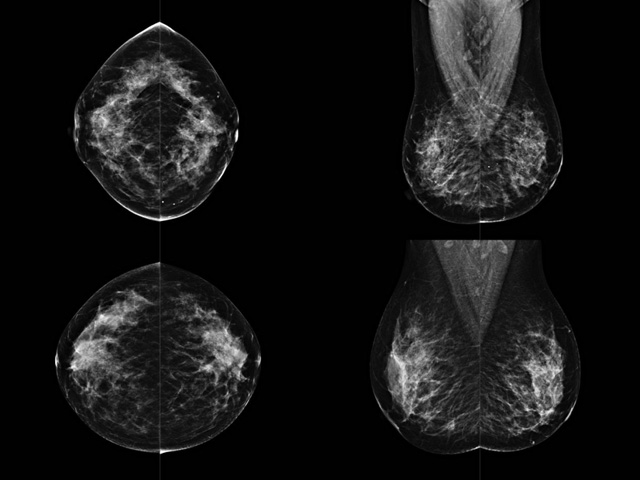

乳腺DR成像設備中非晶硅跟非晶硒兩種平板探測器

乳腺DR成像設備中非晶硅跟非晶硒兩種平板探測器。更要提供優(yōu)質(zhì)的圖像質(zhì)量乳腺的組織結(jié)構(gòu)與厚度各不相同,減少重拍率輻射劑量,,乳腺的主要構(gòu)成組織均為軟組織結(jié)構(gòu),組織之間密度十分相似,缺乏天然對比度。選擇軟X線攝影技術(shù)獲得良好對比度的乳腺結(jié)構(gòu)影像。增加各組織對X線的吸收差異。乳腺攝影測和分類,平板探測器的像素尺寸范圍應在50到100μm之間。特別是微鈣化灶可以小到100到200μm,平板探測器都必極小微鈣化灶進行成像。

乳腺DR是利用X光來做檢查,在一瞬間將被檢測到的位置投影出來,因為是瞬間的輻射,所以只需要0.5秒的時間。因此對病人的輻射很低,大約是0.023mSv,比國家的標準要低得多。DR系統(tǒng)由 X線、發(fā)生裝置、直接轉(zhuǎn)換平板探測器、系統(tǒng)控制器、影像監(jiān)視器、影像處理工作站等組成。能檢查胸腔積液、肺結(jié)核、大葉性肺炎、肋骨骨折等。心室增大、主動脈擴張、主動脈瘤等心臟病。腹部病變,如腸梗阻、腸穿孔等,DR上可見液氣平面、膈下游離氣腫。DR表現(xiàn)不正常,要結(jié)合臨床表現(xiàn)、體征、癥狀等綜合分析,結(jié)合CT、彩超、血液分析等,才能作出正確的判斷。